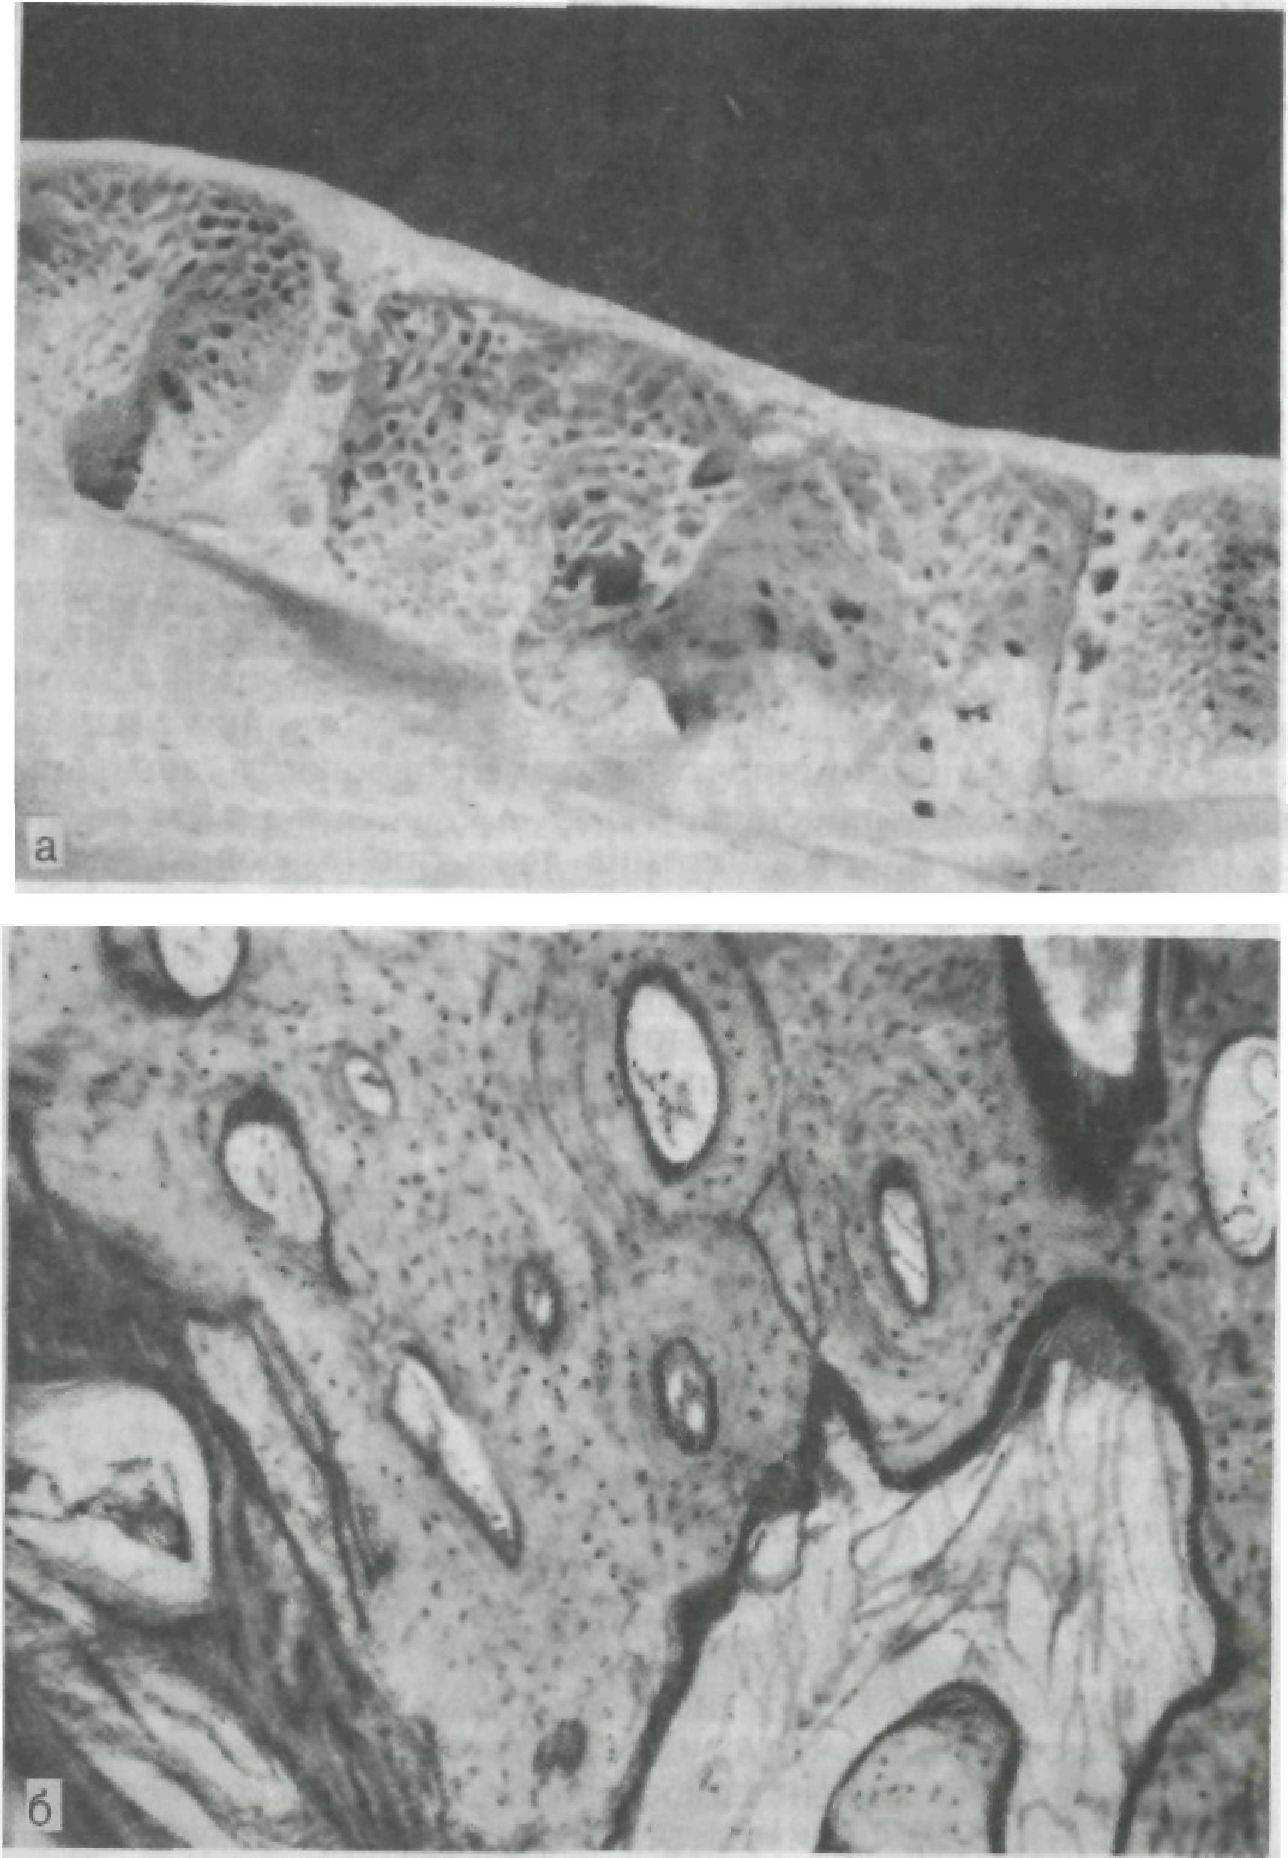

Тонкий слой внутренней компактной пластинки в области верхушки корня в сочетании с изогнутостью балок губчатого вещества, истончение компактного вещества у края альвеолы, наличие большого количества перфорационных отверстий на внутренней поверхности в пришеечных и приверхушечных зонах (рис. 153) и более интенсивный процесс физиологической перестройки в этих же участках топографически связаны с зонами наибольшего пространственного смещения зубов. Зонам повышенной функциональной нагрузки соответствует расположение оппозиционных линий склеивания, ритмичность костеобразователь-

Рис. 153. Продольный распил нижней челюсти (а) и рентгенограммы срезов зубочелюстных сегментов (б).

ного процесса в стенках альвеол. На вестибулооральных срезах выявлено преимущественное расположение в верхней трети длины стенок альвеол поперечно срезанных остеонов, в средней части к ним присоединяются продольно или косо срезанные остеоны (косые остеоны, по А. Л. Шабадашу и А. И. Дойникову). Количество продольных срезанных остеонов возрастает к приверхушечной зоне.

Отсутствие однонаправленности хода остеонов является доказательством сложного комплекса развивающихся деформаций этого участка челюсти в процессе разжевывания пищи. Наличие компактного строения вестибулярных и оральных стенок альвеол позволяет по-новому подойти к пониманию процессов патологической перестройки пародонта при пародонтите, так как процесс перестройки кости протекает по-разному в компактном и губчатом веществе. Гистологические исследования челюстей с явлением очагового пародонтита на фоне частичной адентии подтвердили взаимосвязь патологической перестройки с изменением условий функционирования тканей пародонта, зональным изменением кровообращения.

Отмечено видимое расширение ложа проникающих сосудов и диаметра каналов остеона (гаверсовых каналов), истончение и исчезновение внутренней кортикальной пластики, что превращает компактную костную ткань стенок альвеол в своеобразную «губчатую» кость (рис. 154). Спонгиотизация стенок альвеол у отдельных зубов, находящихся в измененных условиях, очевидно, является одним из характерных признаков функциональной патологической перестройки. Установленная картина перестройки компактного слоя путем частичного или полного рассасывания костного вещества остеонов аналогична описанной в общей патологии Т. П. Виноградовой (1971). Процесс перестройки различен на разных уровнях стенок альвеол. По верхнему краю стенки альвеолы образуется дефект костной пластинки, заполненный грануляционной тканью с остеокластами; сам край стенки представлен грубопучковой костью. Ниже — компактная кость с расширенными каналами остеонов, число которых уменьшается по направлению к основанию альвеолы. На внутренней поверхности стенок расширенных каналов определяются пазухи и участки гладкой резорбции. Одновременно в наружных слоях остеона имеется обычная пластиночная кость с тонкими, извилистыми линиями склеивания, что свидетельствует о проходивших процессах перестройки. В зоне наибольшей патологической перестройки каналы остеонов сливаются между собой, образуя большие полости, стенки которой имеют неровные контуры с участками гладкой резорбции. Расширенные просветы каналов соединены между собой костными мостиками. В нижележащих участках встречаются остеоны с сохраненным пластинчатым строением и интенсивно окрашенными ровными линиями склеивания, что свидетельствует о параллельно идущем костеобразовательном процессе.

Рис. 154. Очаговый пародонтит.

а — спонгиотизация компактной костной ткани стенок альвеол вследствие расширения сосудистых каналов. Вид альвеол сверху; б — костные структуры стенок альвеол в зоне функциональной патологической перестройки. Микрофото. Х80.